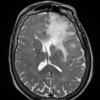

NEOPLASMS (GLIAL)

Astrocytoma, IDH-mutant, WHO Grade 2 (9)